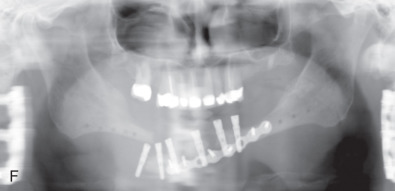

All of these systems allowed for convalescent function – life without MMF. RIF had the potential of dramatically shortening the course of treatment. However, its use was highly technique-sensitive with a steep learning curve. Thus, the incidence of complications increased dramatically due to operator error. Complications related to inadequate reduction – “the OIF” (open internal fixation … without the reduction) ( Figs. 1.16.1–1.16.3 ), inadequate fixation ( Figs. 1.16.4–1.16.7 ) and surgical misadventure ( Fig. 1.16.8 ) began to appear. Indeed, by the early 1990s operator error was the number one cause of mandibular fracture complications. Quite obviously, RIF is very unforgiving. When done poorly, one has a rigidly fixed mistake. The latest series of misadventures are related to the use of IMF screws. Bone-anchored arch bars will most likely be next. Not all believe that RIF and convalescent function is cost-effective with respect to the increased cost, potential for complications, and patient acceptance.

As has been noted, this largely depends on what one considers a complication. Some feel that minor complications – loss of teeth, exposure of hardware, exfoliation of bone and modest delay to union – do not count, so long as union and some semblance of functional occlusion is achieved. Others consider complications to include anything that delays union or results in a suboptimal result. For example, transoral miniplate fixation of angle fractures has a 22% minor complication rate – exposure of hardware, loose screws, wound dehiscence – which can be simply managed in an office setting and do not affect the final outcome. The same treatment has a low (2%) major complication rate requiring return to the OR and major surgery in the form of application of additional RIF and/or bone graft.